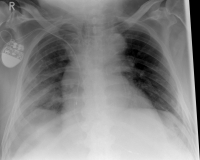

Rib Fractures

The rib fracture is a common injury to the chest. It occurs frequently in (car) accidents, falls during cycling and contact sports. Due to their anatomical position, especially the 4th - 9th ribs are affected.

As a rule, the rib fracture is diagnosed by X-ray. In severe cases or ambiguous X-ray findings, a layer imaging, for example computer tomography (CT), can also be performed.

Pneumothorax / tension pneumothorax

In some cases, the sharp rib fragments cause lung or outer chest wall injuries. As a result, air can enter the gap between the lung and chest wall and cause a so-called pneumothorax, which must be treated by drainage.

Hemothorax

If blood accumulates in the gap between the lungs and the chest wall due to the injury of a blood vessel or the lungs, this is called hematothorax. If there is still air in the gap, it is a hematopneumothorax. Both the hematopoietic and the hematopneumothorax must often be treated with a drainage.